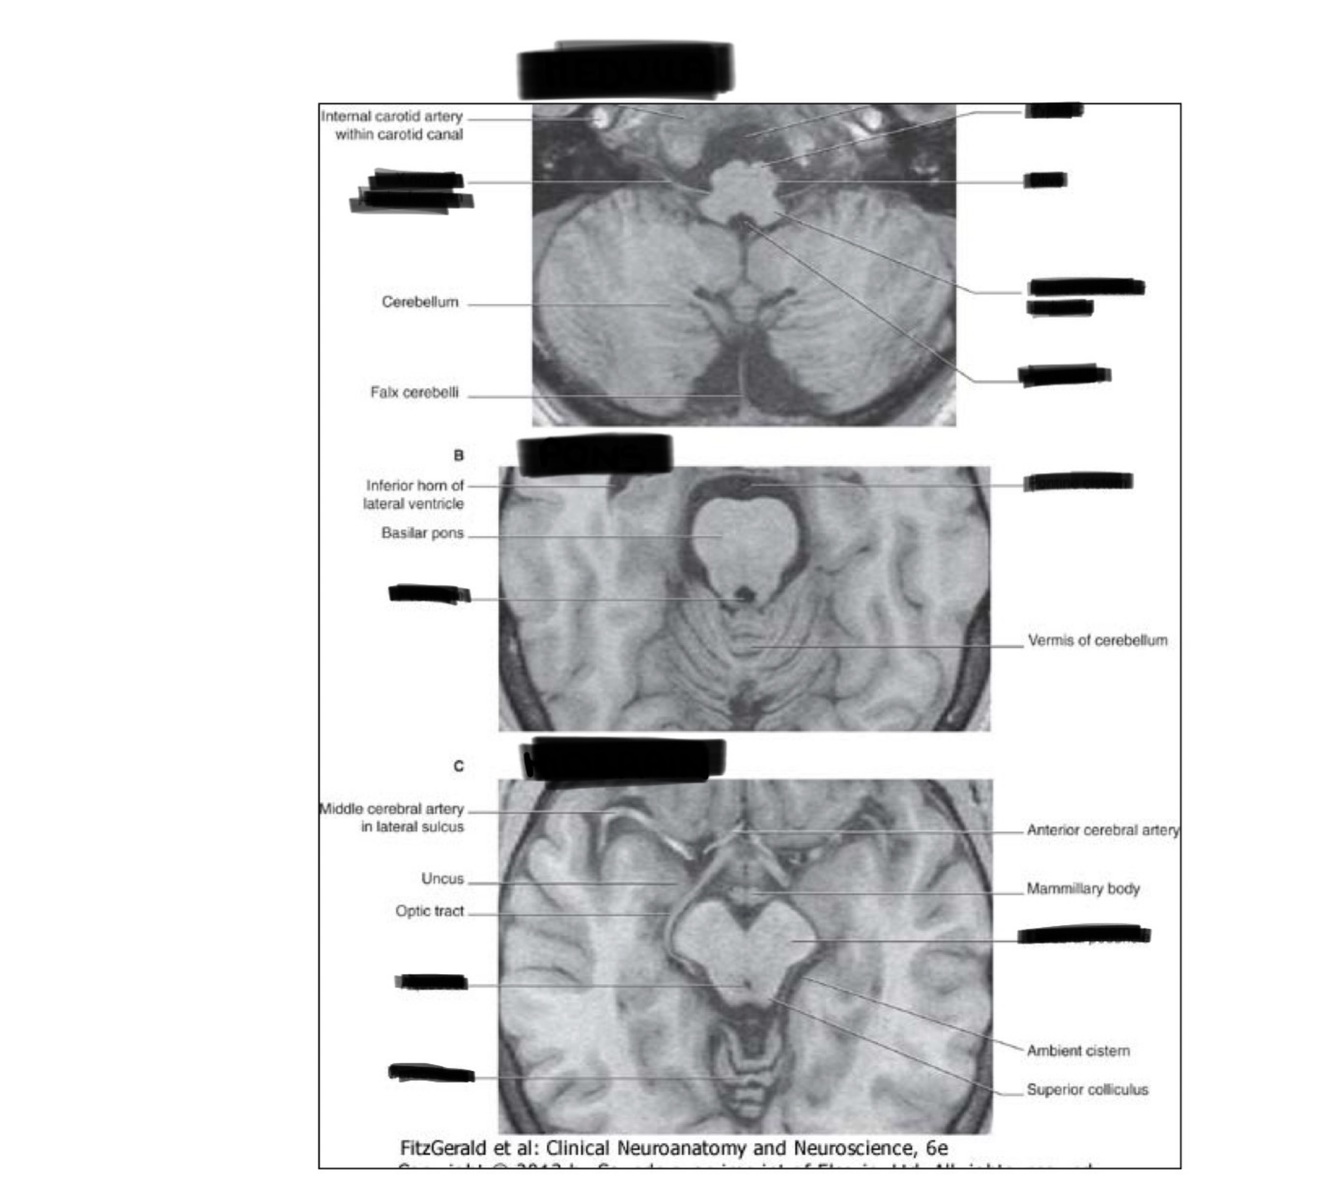

To which part corresponds each image? Name the structures

A. Medulla B. Pons C. Midbrain

Medulla parts

26

Name the structure and what is marked

Medulla and inferior olives

27

Name these structures

Cerebellum and medulla

28

1. TEGMENTUM 2. Basilar pons